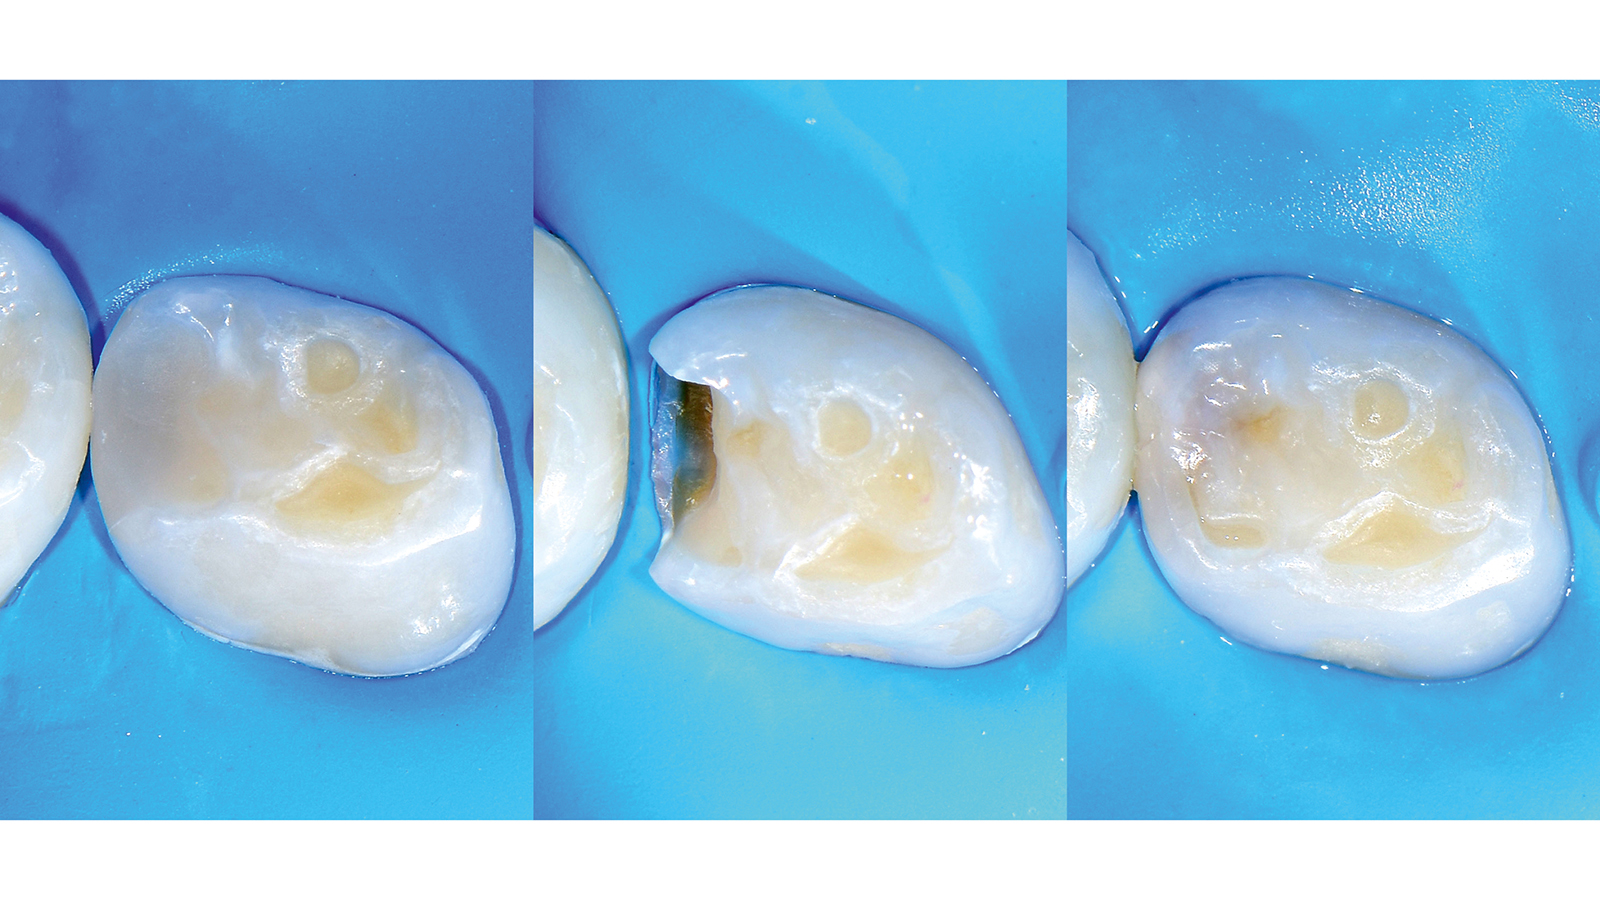

Charisma Bulk Flow ONE combines the self-levelling effect of a flowable material with a high curing depth and good stability after application. This allows to place increments of up to 4 mm inside a cavity. With Charisma Bulk Flow ONE dentists can reduce treatment time without the need for shade selection or the placement of a universal composite as an additional capping layer. With its range of indications from bulk filling through cavity lining to fillings in primary teeth, the efficient restoration procedure is further enhanced by the equally reliable and versatile bonding solution GLUMA Bond Universal.

In an external study done by Prof. Nate Lawson Charisma Bulk Flow ONE was one of the materials which showed the highest depth of cure and at the same time the lowest translucency of the tested bulk fills. Charisma Bulk Flow ONE can be placed safely in up to 4 mm bulk layers without the need of an additional capping layer.

When is Charisma Bulk Flow ONE recommended to be used with or without capping lay-er?

Using Charisma Bulk Flow ONE without capping layer is beneficial in all clinical cases where a flowable viscosity is ideal during placement, e.g. slot or small cavities or those with tunnel preps, class III restorations with intact labial wall or class V restorations. From a patient perspective, Charisma Bulk Flow ONE is furthermore ideal in cases with little patient compliance or time. By preference or if patients demand a natural morphology, Charisma Bulk Flow ONE can always be used with capping layer, too. Using Charisma Classic, Charisma Diamond or Charisma Topaz on top might be advisable in big cavities or cusp replacements.